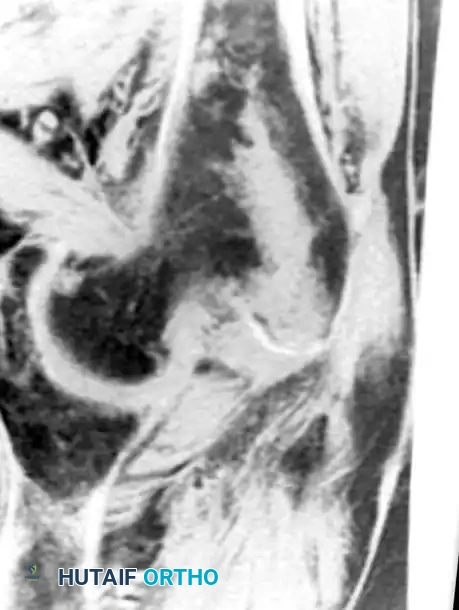

لا تقتصر قوة الرنين المغناطيسي على مفصل الورك فحسب، بل تمتد لتشمل المفاصل الأخرى كالركبة، مما يثبت فعالية هذه التقنية في كشف أدق التفاصيل التشريحية والمرضية في العظام والغضاريف. نستعرض هنا بعض الأمثلة التي توضح دقة الرنين المغناطيسي في تشخيص إصابات المفاصل:

هذه الصور تؤكد بما لا يدع مجالا للشك أن الاعتماد على الرنين المغناطيسي يوفر خريطة طريق واضحة للطبيب المعالج، سواء كان يتعامل مع كيس زلالي، أو كدمة عظمية، أو كسر خفي في صفيحة النمو، أو آفة غضروفية، مما ينعكس إيجابا على دقة التشخيص في مفصل الورك والمفاصل الأخرى.